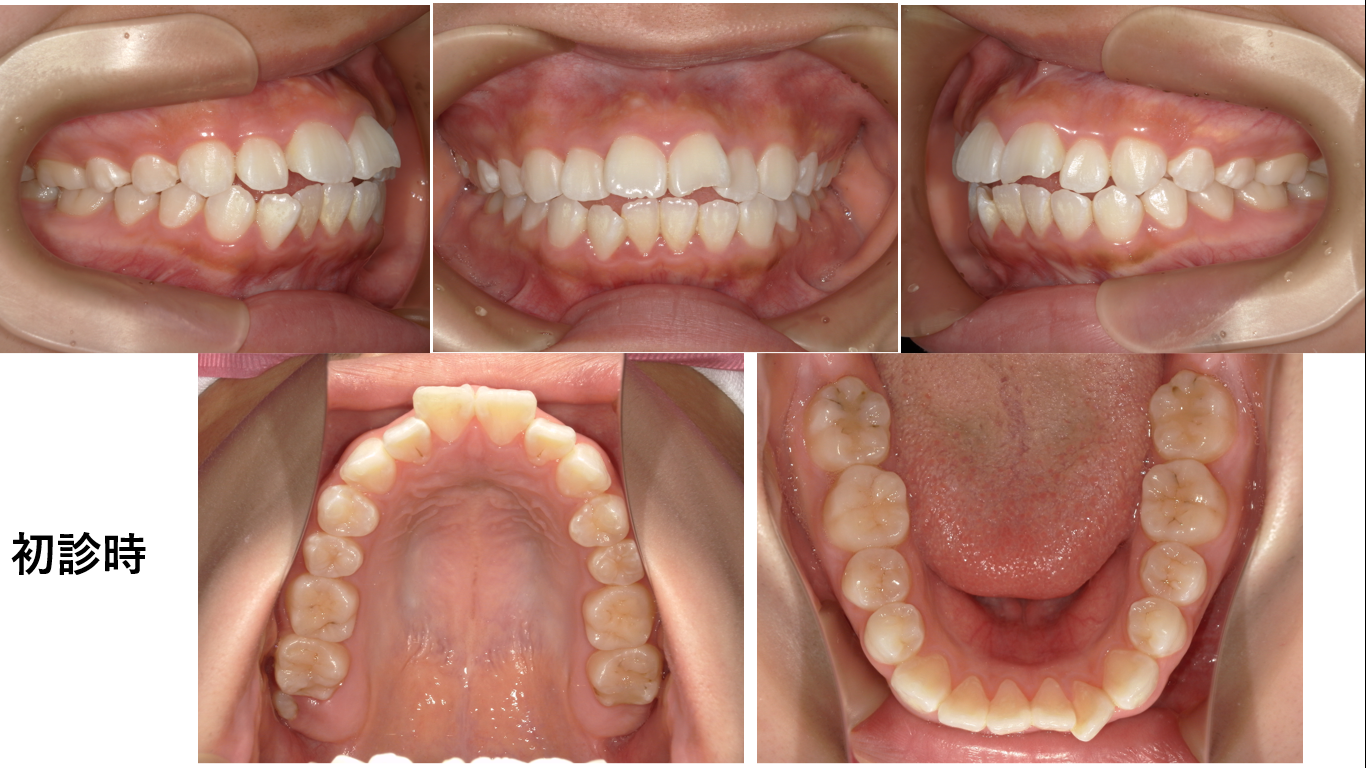

矯正症例141 AngleⅠ級 上下顎前突、ガミースマイル、口ごぼ

初診時15歳、治療期間3年、抜歯部位:上下顎4番、8番、治療費総額102万円(税込み)この症例も患者さんからHP掲載の許可を得ています。